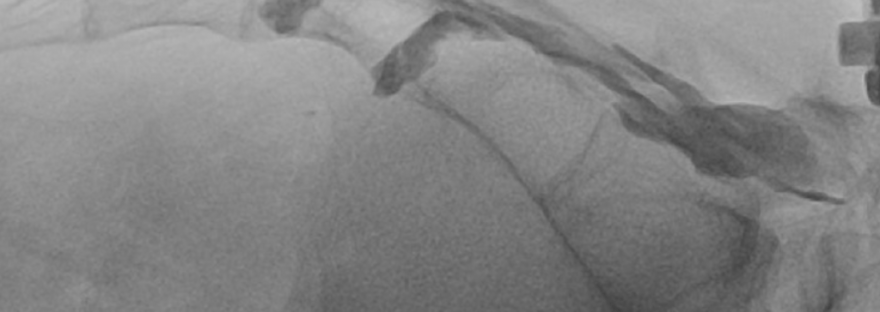

L’infiltrazione epidurale sacrale può aiutare a ridurre l’infiammazione e controllare il dolore.

Rappresenta, nelle mani di personale specializzato una proceduta mini-invasiva e sicura eseguibile anche a livello ambulatoriale.